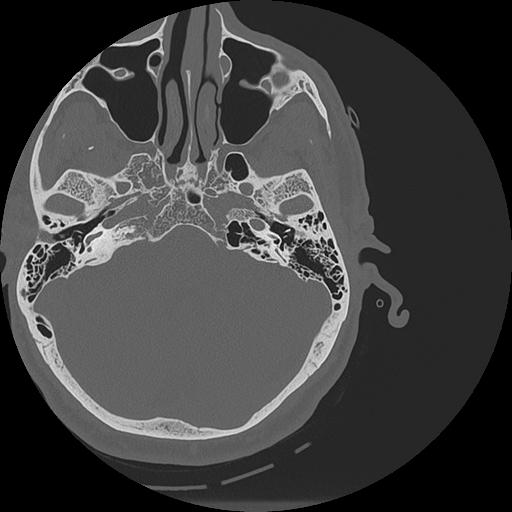

7 HUESO,,Vol,0.5,HUESO,,